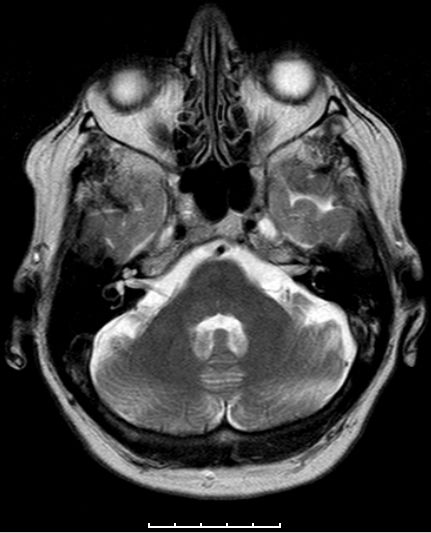

| Adenom | 78jährige Frau. Hypophysenadenom

seit 2 Jahren bekannt. Jetzt Deviation des rechten Auges und Kopfschmerzen.![]() |

![]() Das Adenom ist in die Keilbeinhöhle eingewachsen. |

![]() Infraselläre Ausbreitung mit Ummauerung der Arteria carotis interna rechts. | ||||||||||||||||||||||||||